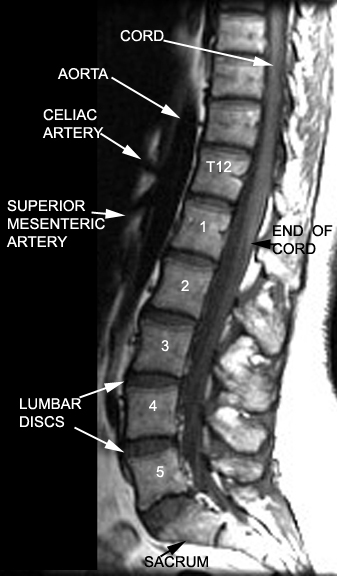

| Image10 | MR Spine | Identify Vertebrae and adjacent structures | Answer |

| Image11 | MR Spine - T2 weighted | Identify Vertebrae and adjacent structures | Answer |